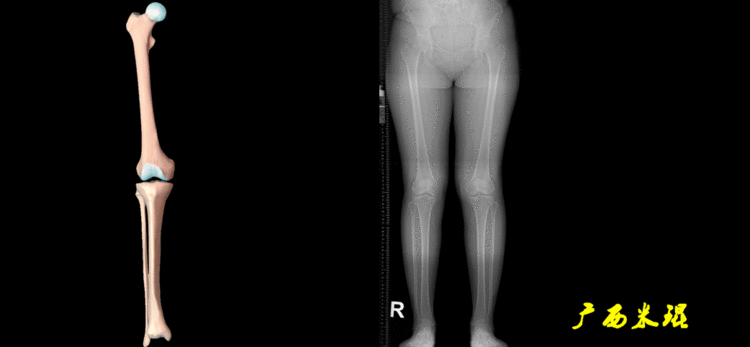

开始接触时可能我们对这些轴有点混乱,通过下面的这张图片就能清楚的了解下肢几个轴之间的关系。

4、画出与机械轴相关的角度股骨近端外侧角(LPFA):沿股骨头中心与大粗隆最高点划一直线,连接股骨头中心与膝关节中心划一直线(机械轴),两者之间形成的外侧夹角,正常为90°±5°。

股骨远端外侧角(mLDFA):股骨内外侧髁远端切线(关节线)与股骨头和膝关节中心的连线(机械轴)两者之间形成的外侧夹角,正常为87°±3°。

胫骨近端内侧角(mMPTA):胫骨内外侧平台切线(关节线)与股骨头和膝关节中心的连线(机械轴)两者之间形成的内侧夹角,正常为87°±3°。

胫骨远端外侧角(mLDTA):胫骨远端切线(关节线)与下肢力线(机械轴)两者之间的外侧夹角,正常为89°±3°。

5、画出与解剖轴相关的角度解剖股胫角(aFTA):股骨干下段轴线(解剖轴)与胫骨上段轴线(解剖轴)在膝关节所形成的夹角,正常为174°±1°。膝关节OA的畸形常常由于一侧软组织及关节的过度磨损所致,临床多为内侧磨损过度,因此表现为轻度膝内翻畸形,X线表现为解剖股胫角小于174°,而胫骨角正常。

解剖股骨远端外侧角(aLDFA):股骨干下段轴线(解剖轴)与股骨内外侧髁远端切线(关节线)在膝关节外侧所形成的夹角,正常为81°±2°。大多数膝外翻患者的畸形发生于股骨下端,表现为股骨远端外侧角小于正常值。

解剖胫骨近端内侧角(aMPTA):胫骨内外侧平台切线(关节线)与胫骨解剖轴两者之间形成的内侧夹角,正常为87°±3°。由于胫骨解剖轴与机械轴几乎一致,所以一般解剖胫骨近端内侧角与机械胫骨近端内侧角一致。

解剖胫骨远端外侧角(aLDTA):胫骨远端切线(关节线)与胫骨解剖轴两者之间的外侧夹角,正常为89°±3°。由于胫骨解剖轴与机械轴几乎一致,所以一般解剖胫骨远端内侧角与机械胫骨远端内侧角一致。

解剖胫骨近端外侧角(也叫aMPTA):胫骨干上段轴线与胫骨平台切线(关节线)在膝关节外侧所形成的夹角,常称为胫骨角,正常为87°±3°。大多数膝内翻患者的畸形发生于胫骨上端,表现为胫骨角大于90°。严重的膝内翻畸形发生在整个下肢,股骨干及胫骨干都有可能形成向内弯曲的弧形。

6、其他角度胫骨股骨关节线夹角(JLCA):胫骨近端关节线与股骨远端关节线之间的夹角,正常生理状态下几乎为0°。当JLCA>2°时提示异常,通常为韧带松弛或者软度磨损丢失所致。

股骨解剖机械轴角(aMFA):股骨解剖轴与机械轴形成的夹角,正常为6°±1°。

股骨垂直机械轴角(MA):股骨机械轴与身体垂直轴形成的外翻角,正常为3°。

最常见的下肢畸形发生于冠状面,即膝内外翻畸形,冠状面的对线异常通过应用“对线异常检验”进行分析,机械轴的偏移(MAD)表现为对线异常。

膝内翻是指下肢力线通过膝关节中心点内侧,距中点2mm以上,偏内超过15mm为显著膝内翻。膝外翻是指下肢力线通过膝关节中心点外侧,距中点2mm以上,偏外超过10mm为显著膝外翻。

2、判断畸形的部位画出下肢全长片中的机械轴和力线轴,确定畸形来自股骨、胫骨还是关节内。首先我们确认股骨机械轴及mLDFA,超出范围为股骨畸形;然后我们确认胫骨机械轴及MPTA,超出范围为胫骨畸形;最后我们确认关节线的汇聚关系JLCA,超出范围为关节内畸形。